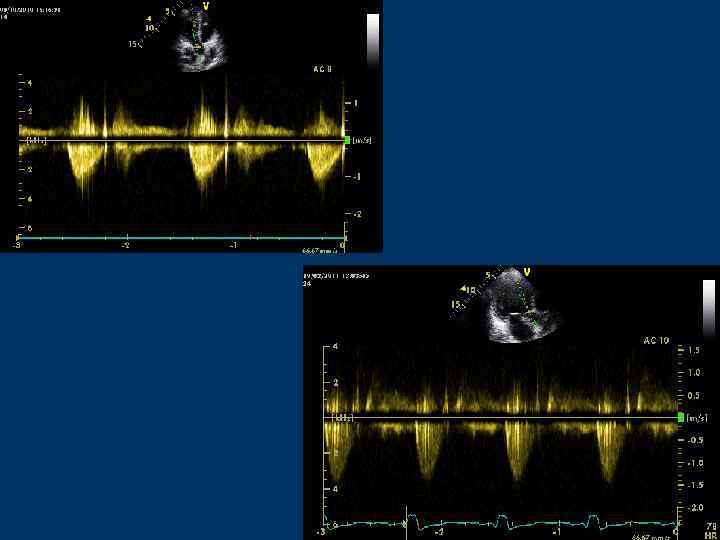

PW CW

Continuous Wave Doppler